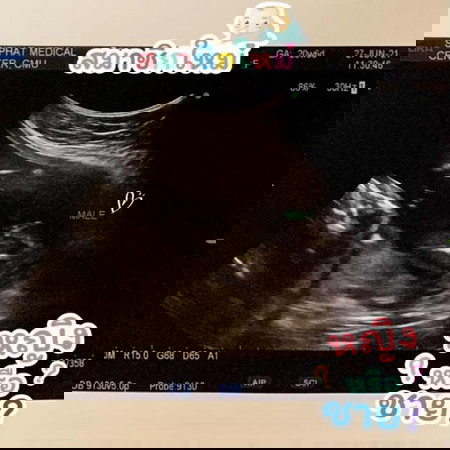

ลูกชายคนแรกครับผม #ทีมพฤจิกายน แม่ๆบ้านอื่นทราบเพศกันหรือยังคะ บ้านนี้รู้ตั้งแต่ตอนตรวจ NIFTY แต่ก็ยังตื่นเต้นมากๆตอนไปอัลตราซาวด์ น้องนอนอ้าขาโชว์คุณหมอเลยครับ คุณพ่อคุณแม่พาเพื่อนๆมาแชร์มาโชว์ผมกันได้นะค้าบบบ 🥰🥰🥰

ทีมพฤศจิ เพิ่งรู้วันนี้เลยค่ะ ป้าหมอบอกผู้ชาย 100% เลย🥰🥰